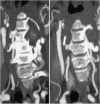

We report a case of a giant intra and extradural cervical schwannoma in a patient affected by a severe myelo-radiculopathy. Clinical features, diagnosis and the issues concerning the surgical management of this benign tumor are discussed. We also review similar cases previously reported in the literature. A 50-year old caucasian woman was complaining of a 1 year of neck pain and worsening motor impairment in all four limbs causing the inability to walk. Neuroradiological assessment revealed a suspected schwannoma involving the nerve roots from C3 to C5, compressing and deviating the spinal cord. The vertebral artery was also encased within the lesion, but still patent. A posterior cervical laminectomy with a microsurgical extradural resection of the lesion was performed. Moreover, an accurate dissection of the lesion from the vertebral artery and the resection of the intraspinal component was achieved. Vertebral fixation with screws on the lateral masses of C3, C5 and C6 and a hook on C1 was performed. The procedure was secured using electroneurophysiological monitoring. A progressive improvement of the motor functions was achieved. A cervical post-contrast MRI revealed optimal medullary decompression and a gross-total resection of the lesion. Schwannomas are benign, slowly growing lesions which may cause serious neurological deficit. Early diagnosis is necessary and it maybe aided by imaging studies such as MRI or CT. The accepted treatment for these tumors is surgical resection and, when indicated, vertebral fixation.